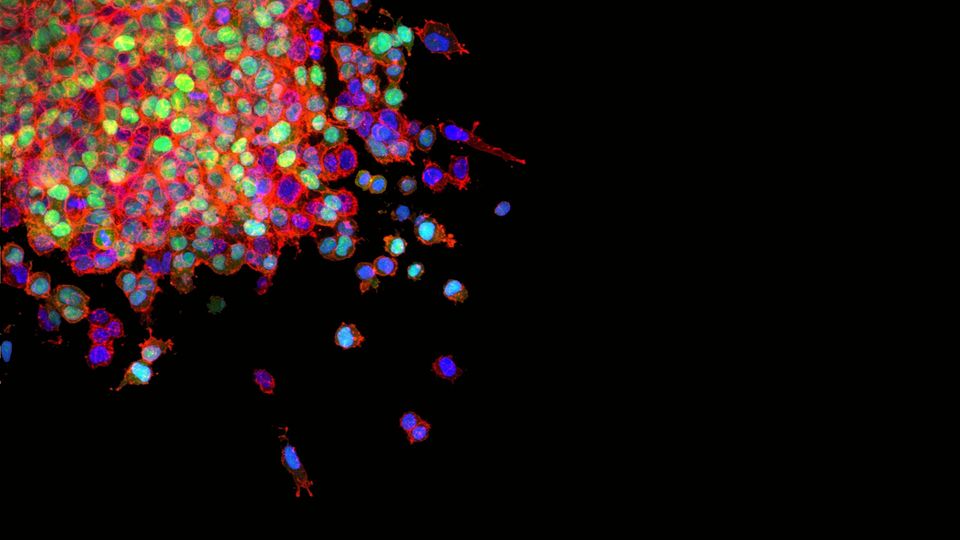

Rearranging Tumor Cell Structures Could Advance Cancer Treatments

Rearranging the location of lipid droplets in cancer cells can increase the effectiveness of cell starvation.

University of Cincinnati researchers are pioneering a new biomedical technique: rearranging and altering the physical structure and location of subcellular organelles themselves.

UC’s Jiajie Diao, PhD, and colleagues have published new research showing a proof of concept that rearranging the location of lipid droplets within cells can increase the effectiveness of cell starvation, making it a potential cancer treatment. The research was published as the November cover story in the journal Trends in Biotechnology.

“This was important to look at, particularly for certain cancer cells, because the way the cancer cells or tumors will be targeted for treatment is to try to starve the cell to kill it,” said Diao, associate professor in the Department of Cancer Biology in UC’s College of Medicine. “However, cancer cells also have these lipid droplets, so they will use lipid droplets to supply food and energy. We’re trying to find a way to better cause starvation of tumor cells.”

Lipid droplets are naturally evenly distributed in cells. The researchers looked for a way to group the lipid droplets together and keep them from moving toward the mitochondria during cell starvation. To accomplish this, they engineered a sequence of proteins that includes one peptide linked to cancer cell lipid droplets and another peptide designed to be activated under blue light stimulation.

“When activated by light, the peptides will eventually bring all the lipid (droplets) together and lock them up,” Diao said. “It’s like a light-active glue, and they form a big chunk inside the cell.”

Researchers found this approach of locking up lipid droplets away from mitochondria led to more complete cell starvation because the cancer cells had no energy reserves. In practice, this led to a slowing of tumor progression in cell lines and animal models.